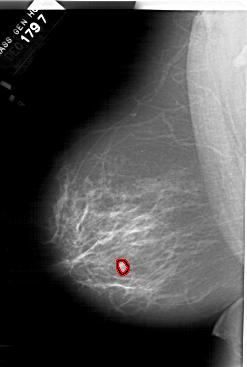

A_1518_1.LEFT_MLO

LEFT_MLO LINES 6601 PIXELS_PER_LINE 4441 BITS_PER_PIXEL 12 RESOLUTION 43.5 OVERLAY

FILE: A_1518_1.LEFT_MLO.OVERLAY

TOTAL_ABNORMALITIES 1

ABNORMALITY 1

LESION_TYPE MASS SHAPE LOBULATED MARGINS ILL_DEFINED

ASSESSMENT 4

SUBTLETY 2

PATHOLOGY BENIGN

TOTAL_OUTLINES 1

BOUNDARY